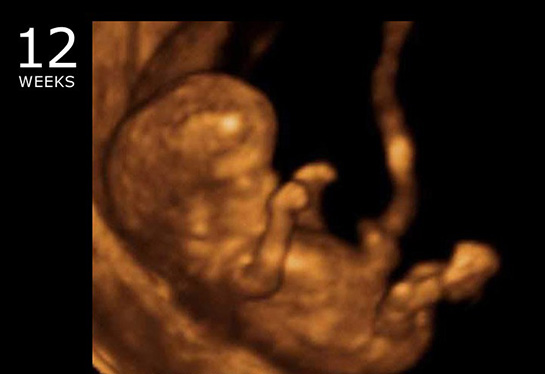

10 haftalık gebelik, hamileliğin ikinci trimesterine geçişin başlangıcını işaret eden önemli bir dönemdir. Bu dönemde, fetüs hızla gelişmekte ve anne vücudunda çeşitli değişiklikler meydana gelmektedir. Bu makalede, 10 haftalık gebeliğin fiziksel ve psikolojik etkileri, fetal gelişim, beslenme önerileri ve dikkat edilmesi gereken noktalar üzerinde durulacaktır. Fetal Gelişim 10. hafta itibarıyla fetüs, yaklaşık 3,5 cm uzunluğundadır ve bu haftada önemli gelişim aşamalarından geçmektedir. Aşağıda fetüsün bu aşamadaki gelişimsel özellikleri sıralanmıştır: